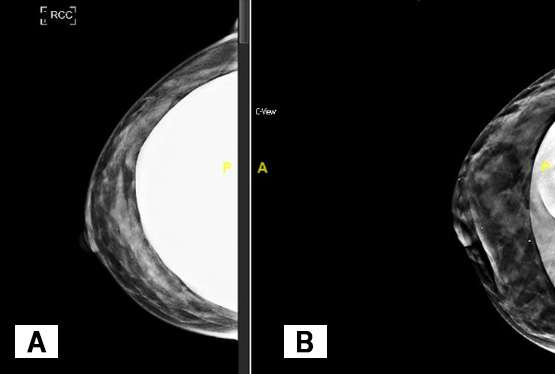

Breast implants appear dense on mammographic images and can obscure normal breast tissue. For patients with breast augmentation, the Mammographic Quality Standards Act recommends two additional views of each breast in addition to the standard views described in the aforementioned text.2 While the standard MLO and CC views are obtained with the implant included and with lighter compression to prevent implant rupture, the additional “implant displaced” views are performed under normal compression with as much of the implant excluded from the image as possible (Figure 3). A closer evaluation of normal breast parenchyma can be assessed on the implant displaced views while the implant included views allow for visualization of both the implant and a general overview of the breast.

Standard craniocaudal implant included view of the right breast

Figure 3: Standard craniocaudal implant included view of the right breast (Figure 3A) and implant displaced craniocaudal view (Figure 3B), which are part of standard mammogram screenings in patients with breast implants.